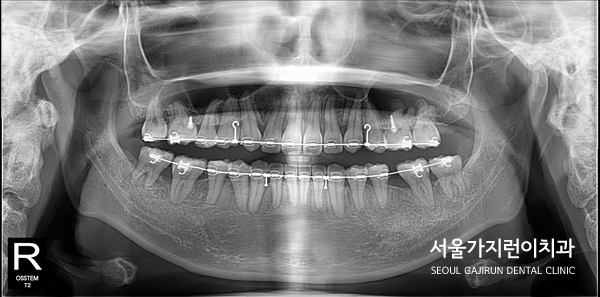

- 정밀 진단: 사랑니의 위치, 방향, 뿌리 형태, 주변 치아와의 관계를 파악하기 위해 CT 및 파노라마 촬영을 진행합니다.

- 교정 장치 부착: 전체 교정 또는 부분 교정 장치를 부착하여 사랑니를 서서히 앞으로 이동시킵니다.

- 사랑니 견인: 발치된 어금니 자리로 사랑니를 끌어당기며, 교합을 맞추고 기능적으로 사용할 수 있도록 배열합니다.